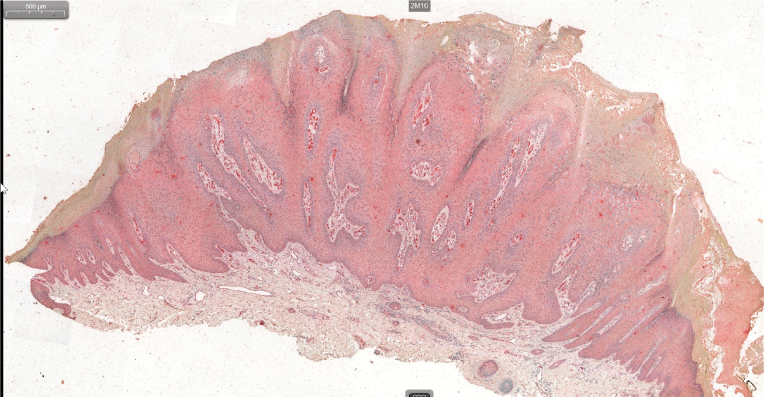

The immunostaining assay showed that CD31+, CD34+ and CD105+ vessel density was significantly higher in skin warts compared to that in normal skin, where the statistical data were represented as mean ± SD (45.71 ± 22.63 vs. 21.27 ± 5.83, p= 0.0062; 59.75 ± 24.93 vs. 17.13 ± 5.67, p<0.001; 29.74 ± 7.09 vs. 6.58 ± 1.89, p<0.001; for CD 31 and CD 34, CD105 respectively; (Figures 1 and 2).

Figure 1A. CD 31+ vessels in the upper dermis (stained red) in a wart sample (×10 original magnification)